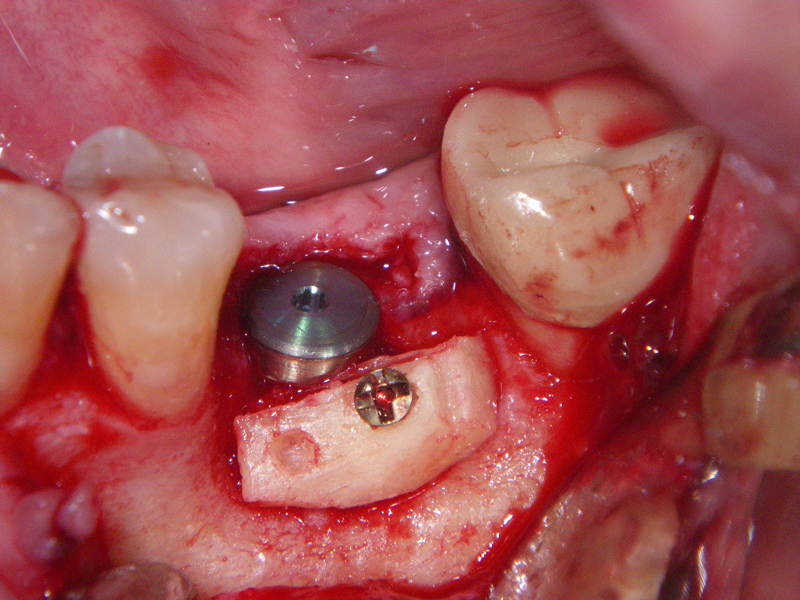

- Stage I: Implant placement/Sealing Screw

- Alveolar Ridge Augmentation

- Bone grafting – autogeneous, alogenic, xenogenic

- Blockgraft